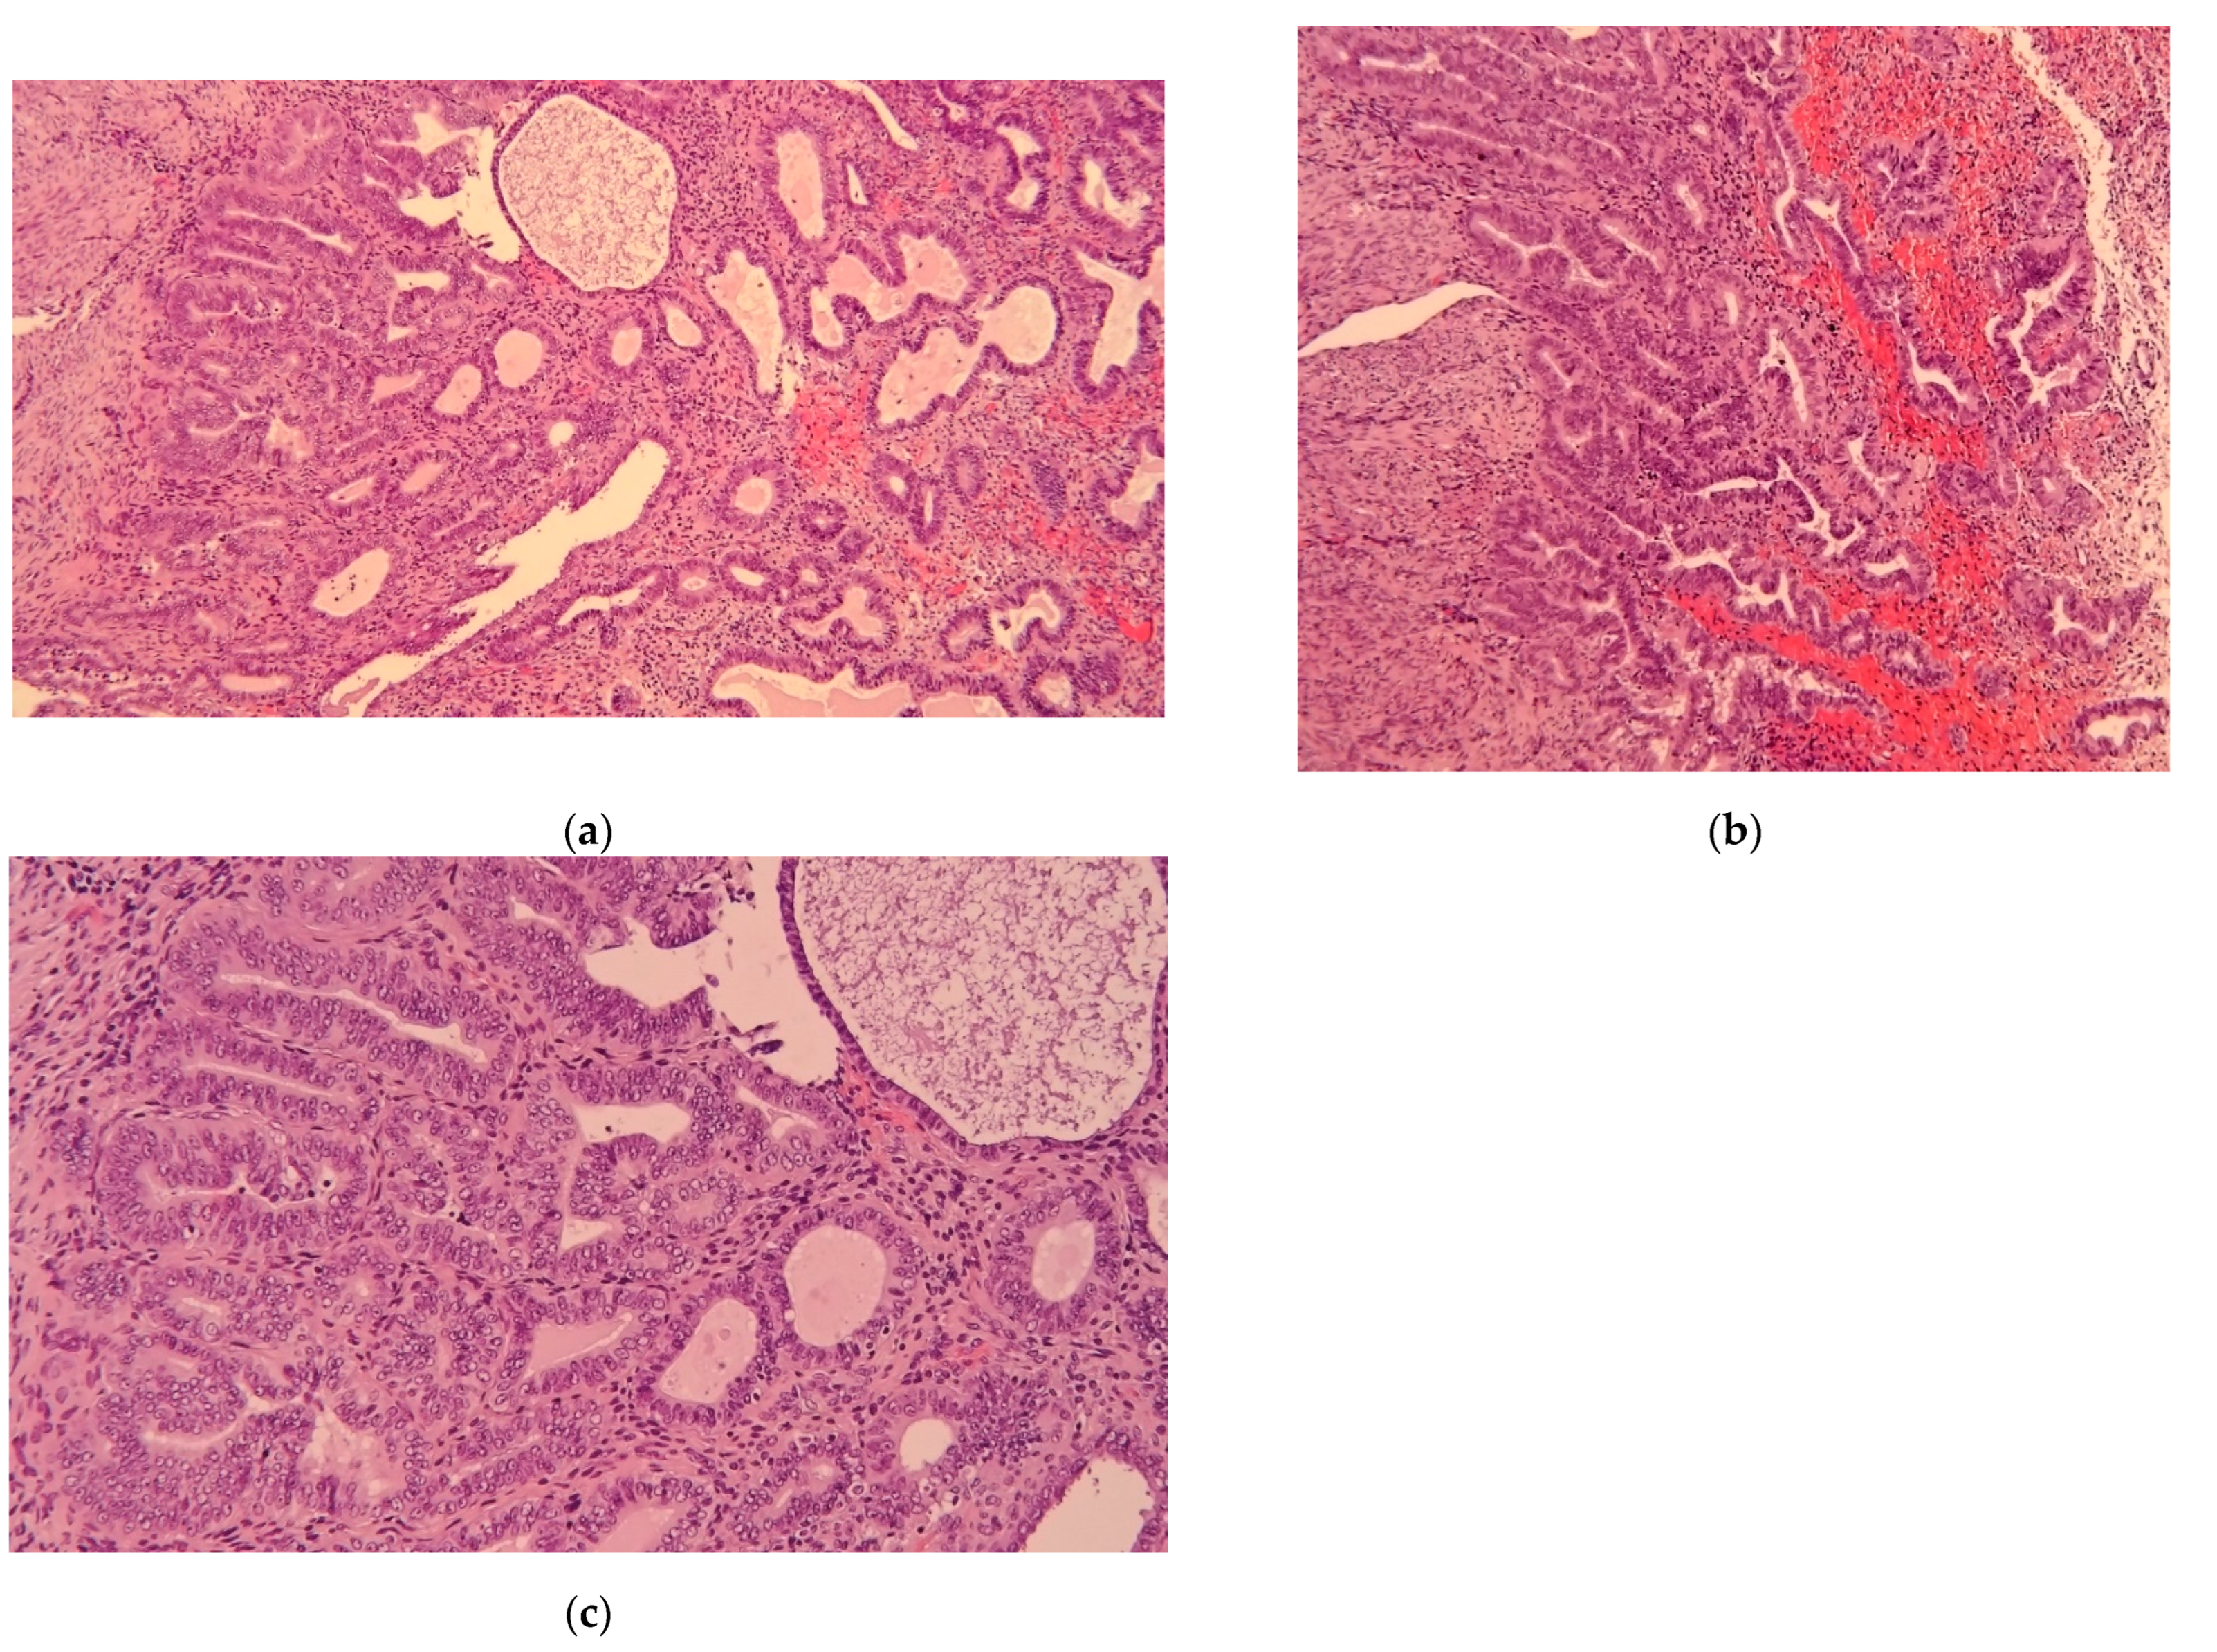

- Histopathological reports on the uterus, most notably the presence of endometrial carcinoma and its features according to WHO 2014 classification [13].